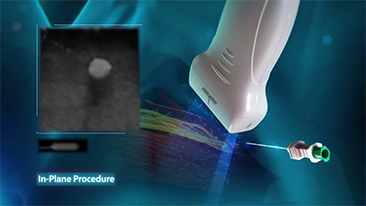

Infolge des Coronavirus haben Krankenh?user und Gesundheitspersonal neue Arbeitsweisen entwickelt, etwa, in Akutbereichen, Social Distancing, strikte Pflicht zum Tragen einer Maske oder anderer pers?nlicher Schutzausr├╝stung (PSE), H?nde waschen und t?gliches Desinfizieren der Ausr├╝stungsgegenst?nde. Tragbare, hochmobile und vielseitige Ger?te kamen f├╝r den Point-of-care (POC) insbesondere dann in den Blick, wenn Stationen und Operationss?le ├╝ber zahlreiche Stockwerke verteilt lagen und der Zugang zu Spezialger?ten schwierig war.